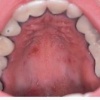

Sümptomid

• igemed veritsevad (19)

• igemed punetavad (21)